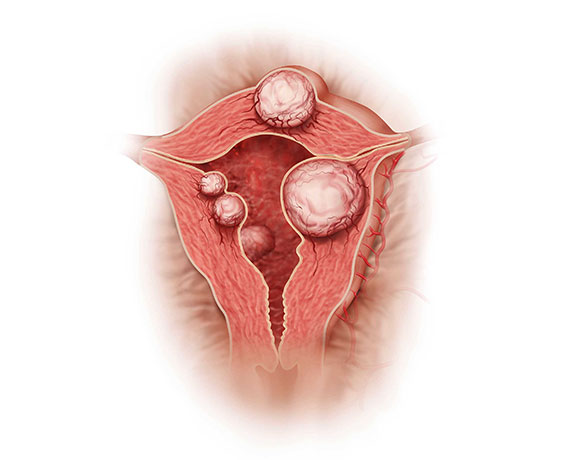

Myomlar (Rahim Urları)

Myomlar, doğurganlık çağında ki kadınlarda görülen kanseröz olmayan yapılardır. Halk arasında ‘rahimde ur’ olarak da bilinirler. Neredeyse her 4 kadından 3’ünde myom gelişir, ancak genellikle herhangi bir şikayete neden olmadıklardan çoğu kişi myomlarının varlığından habersizdir. Myomlar, sıklıkla rutin kontrol sırasında pelvik muayene ya da ultrasonografi ile tespit edilirler. Myomların neden oluştukları tam olarak tespit edilememiş olsa bile genetik faktör, obezite ve doğurgan yaşta olmak bilinen en büyük risk faktörleridir.

Myomların klinik bulguları genellikle lokalizasyonları ile ilişkilidir. Rahim kavitesinin içine doğru büyüyen submüköz myomlar, uzamış ve ağır kanamaya neden olurlar. Bu myomlar aynı zamanda gebe kalmak isteyen kadınlarda da problem yaratırlar. Subseröz myomlar ise rahimin dış kısmına doğru büyüyen myomlardır. Bazen mesaneye bası yaparak idrar ile ilgili şikayetlere neden olabilirler. Eğer rahmin arka tarafına doğru büyürlerse rektuma bası ile kabızlık, spinal sinirlere bası ile bel ağrısına neden olabilirler.

Myomlar, genellikle gebe kalmaya engel olmasalar bile yerleşim yerlerine bağlı olarak spermlerin rahim içine girişlerine ya da tüplerden geçişine engel olabilirler. Yine rahim iç tabakasına yerleşmiş olan myomlar embriyo gelişimini engelleyebilirler. Gebelikte ise myomlar sıklıkla karın ve kasık ağrısı şikayetine neden olurlar. Bazı nadir durumlarda ise düşük ya da erken doğuma sebebiyet verebilirler.

Myomlar, genellikle tedavi gerektirmezler fakat hastada aşırı kanama, anemi, ağrı ya da gebeliğe engel durum oluşturuyorlarsa cerrahi olarak çıkarılmaları gerekir.